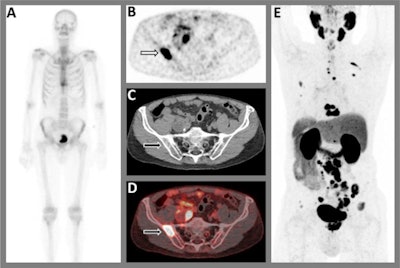

Out of 70 patients with a bone scintigraphy scan negative for metastases on primary staging, at least one bone metastasis was visualized on subsequent F-18 PSMA-PET/CT in 12.9% (9/70) of patients. In patients with low-volume metastatic disease on bone scintigraphy, upstaging to high-volume metastatic disease was reported in four of nine patients (44.4%), and downstaging to absence of bone metastatic disease in two of nine patients (22.2%), according to the findings.